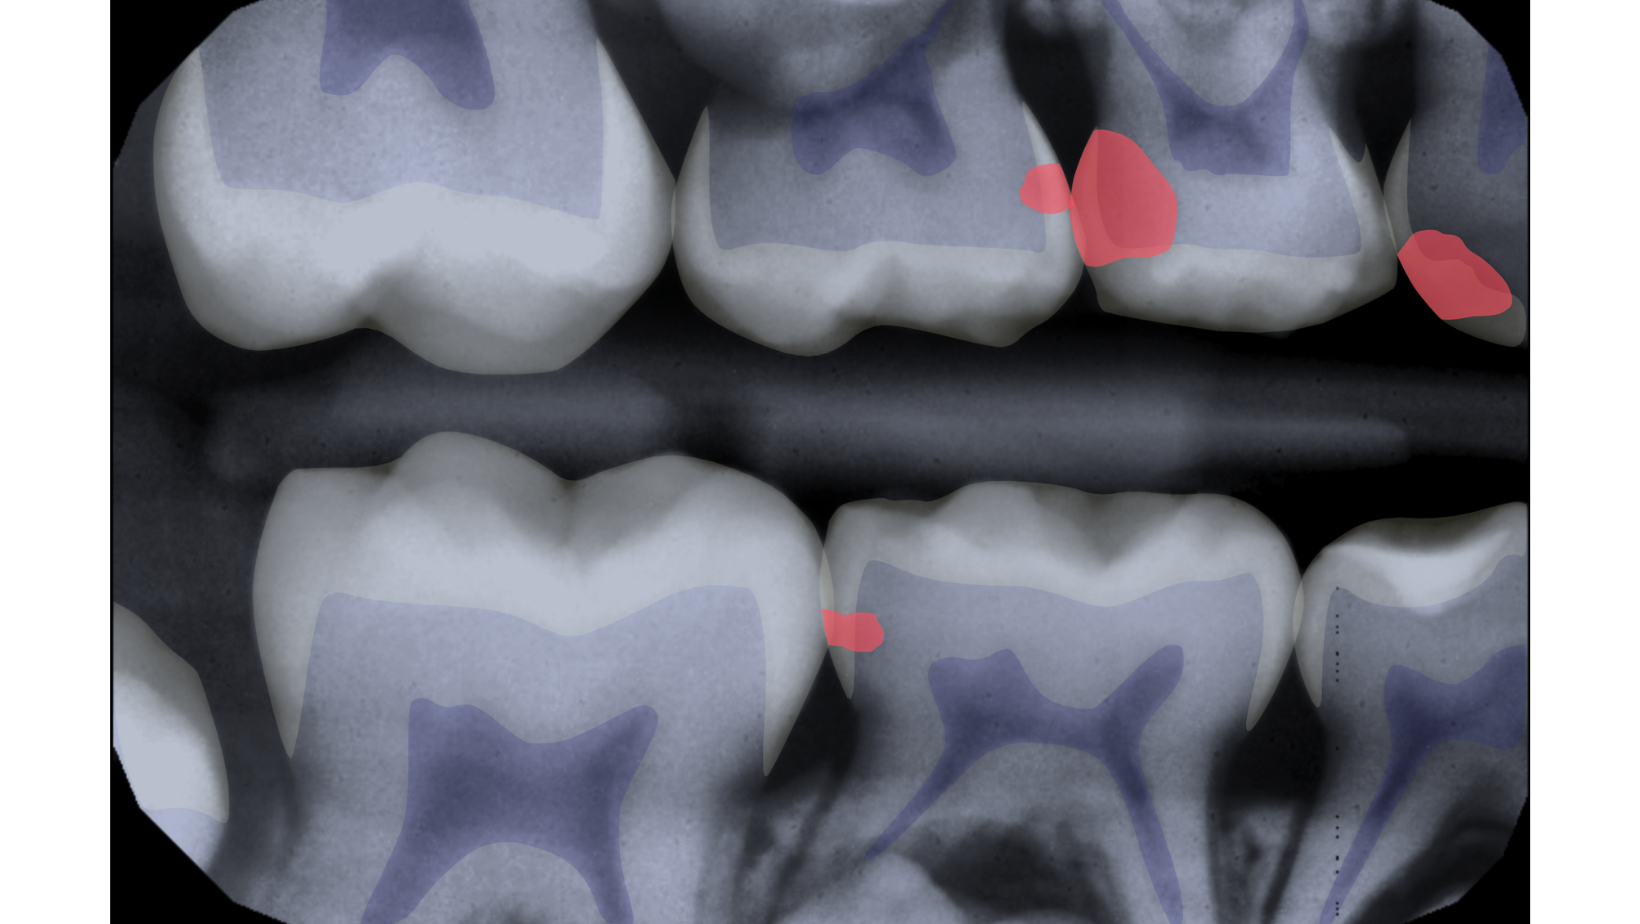

As shown in this blog on patient education, visuals play a pivotal role in education. AI-highlighted shapes (colored in toothparts and potential concerns) ensure that the picture is not just worth a thousand words but is also tailored to the individual patient's needs. This customized approach establishes trust, urgency, and understanding, creating a solid foundation for effective communication.

Videa's pediatric AI represents a groundbreaking solution to the challenges of occlusal caries in mixed dentition. Trained on an extensive dataset comprising 50 times more X-rays than a dentist sees in a lifetime, Videa Dental AI, the FDA clearance, exhibited an 80% improvement in true pediatric caries identification while achieving an overall clinically beneficial detection rate. This advancement ensures a clinically beneficial detection rate, addressing a critical gap in traditional diagnostic approaches.

Occlusal caries, the most common form of decay in mixed dentition, are often poorly identified intraorally. Bitewing radiographs are crucial for detecting lesions in primary molars, but these have limitations. With primary and permanent teeth, angulation and shadowing can occur that isn't typical on an adult radiograph, making it more difficult for providers to use radiographs to diagnose. Due to this, visual examination is realized more heavily in pediatric patients, but visual examination alone may result in a poor diagnosis, with only 48.7% of lesions in the dentin being detected (PubMed).